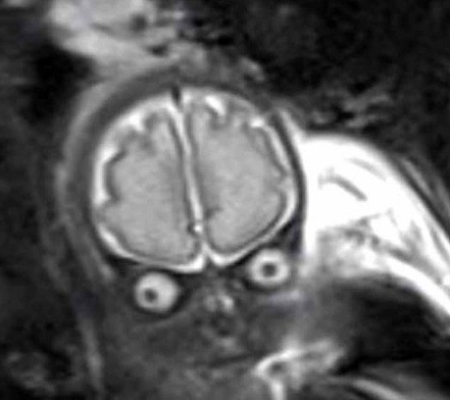

Imagens de bebês em tomografias costumam ser das mais diversas. Entretanto, um novo bebê está deixando todo mundo confuso. Dessa vez, o resultado de uma tomografia fez muita gente acreditar que o feto se parece com um E.T. As informações são do IG.

Os médicos que estavam acompanhando a gravidez dessa mãe, Laura, identificaram uma quantidade preocupante de liquido no cérebro do bebê, Lucas, e pediram que ela fizesse uma tomografia para que pudessem analisar melhor o caso.

O responsável pelo exame avisou Laura e seu marido que eles não veriam a criança como nas tradicionais imagens 2D de outros exames. No entanto, eles não esperavam que veriam dessa forma. De acordo com o canal do YouTube Inside Edition, os pais ficaram em estado de choque, mas, depois, se divertiram com o que viram.

Para os pais, o filho mais se parecia com um E.T do que um feto. Apesar do susto, a imagem da tomografia trouxe uma notícia boa a eles: estava tudo bem com o menino. Laura e o marido contam que a imagem trouxe o alívio e a calma que estavam precisando naquele momento.